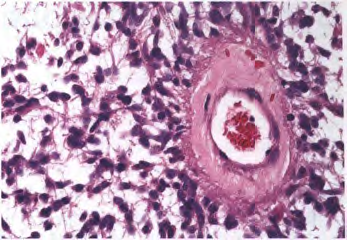

048722bdeb3e09cb23f31f830a8a8524.png

肿瘤组织由致密区及疏松区构成,其中可见Rosenthal纤维